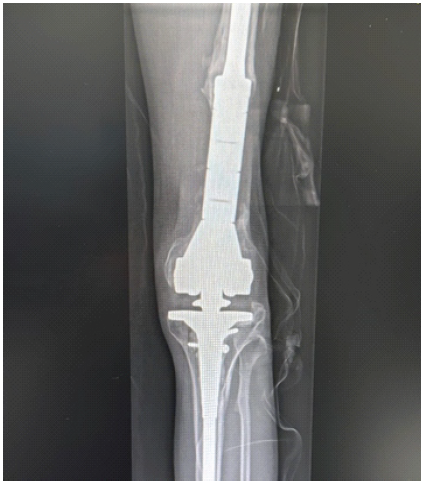

Figure 3: Post-operative radiographs showing distal femoral replacement with restoration of limb length and alignment.

The case was discussed with orthopedic trauma surgeons and arthroplasty surgeons, along with the physiotherapy team, and a DFR followed by a structured physiotherapy plan was planned (Fig. 6).

Figure 6: Final post-operative radiographs showing distal femoral replacement.

For implantation, the final prostheses included a legacy posterior stabilized cemented femoral stem measuring 13.5 mm × 100 mm with an extra-small component, and a cemented tibial component measuring 150 mm × 12 mm with a tibial tray size 2. A polyethylene insert of size 14 was used (Fig. 6). After allowing the cement to cure, final assessment demonstrated a stable knee with full ROM. The quadriceps tendon was repaired, the arthrotomy was closed, and a drain was inserted. The subcutaneous tissues were closed in layers, and the skin was closed with skin clips. Sterile dressings were applied. The patient tolerated the procedure well and was transferred to the recovery room in good condition, with intact distal neurovascular status. He was planned for a few days of inpatient observation for pain control and to initiate full weight-bearing as tolerated. Discharge was planned once medically fit.